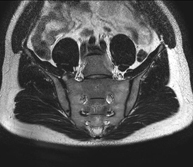

- Sacroiliac MRI

Study specifically designed to assess these joints and their inflammation in patients suffering from ankylosing spondylitis. It is also useful in patients with trauma and possible fractures of the sacrum and coccyx. It lasts approximately 16 minutes. It is a radiation-free procedure.